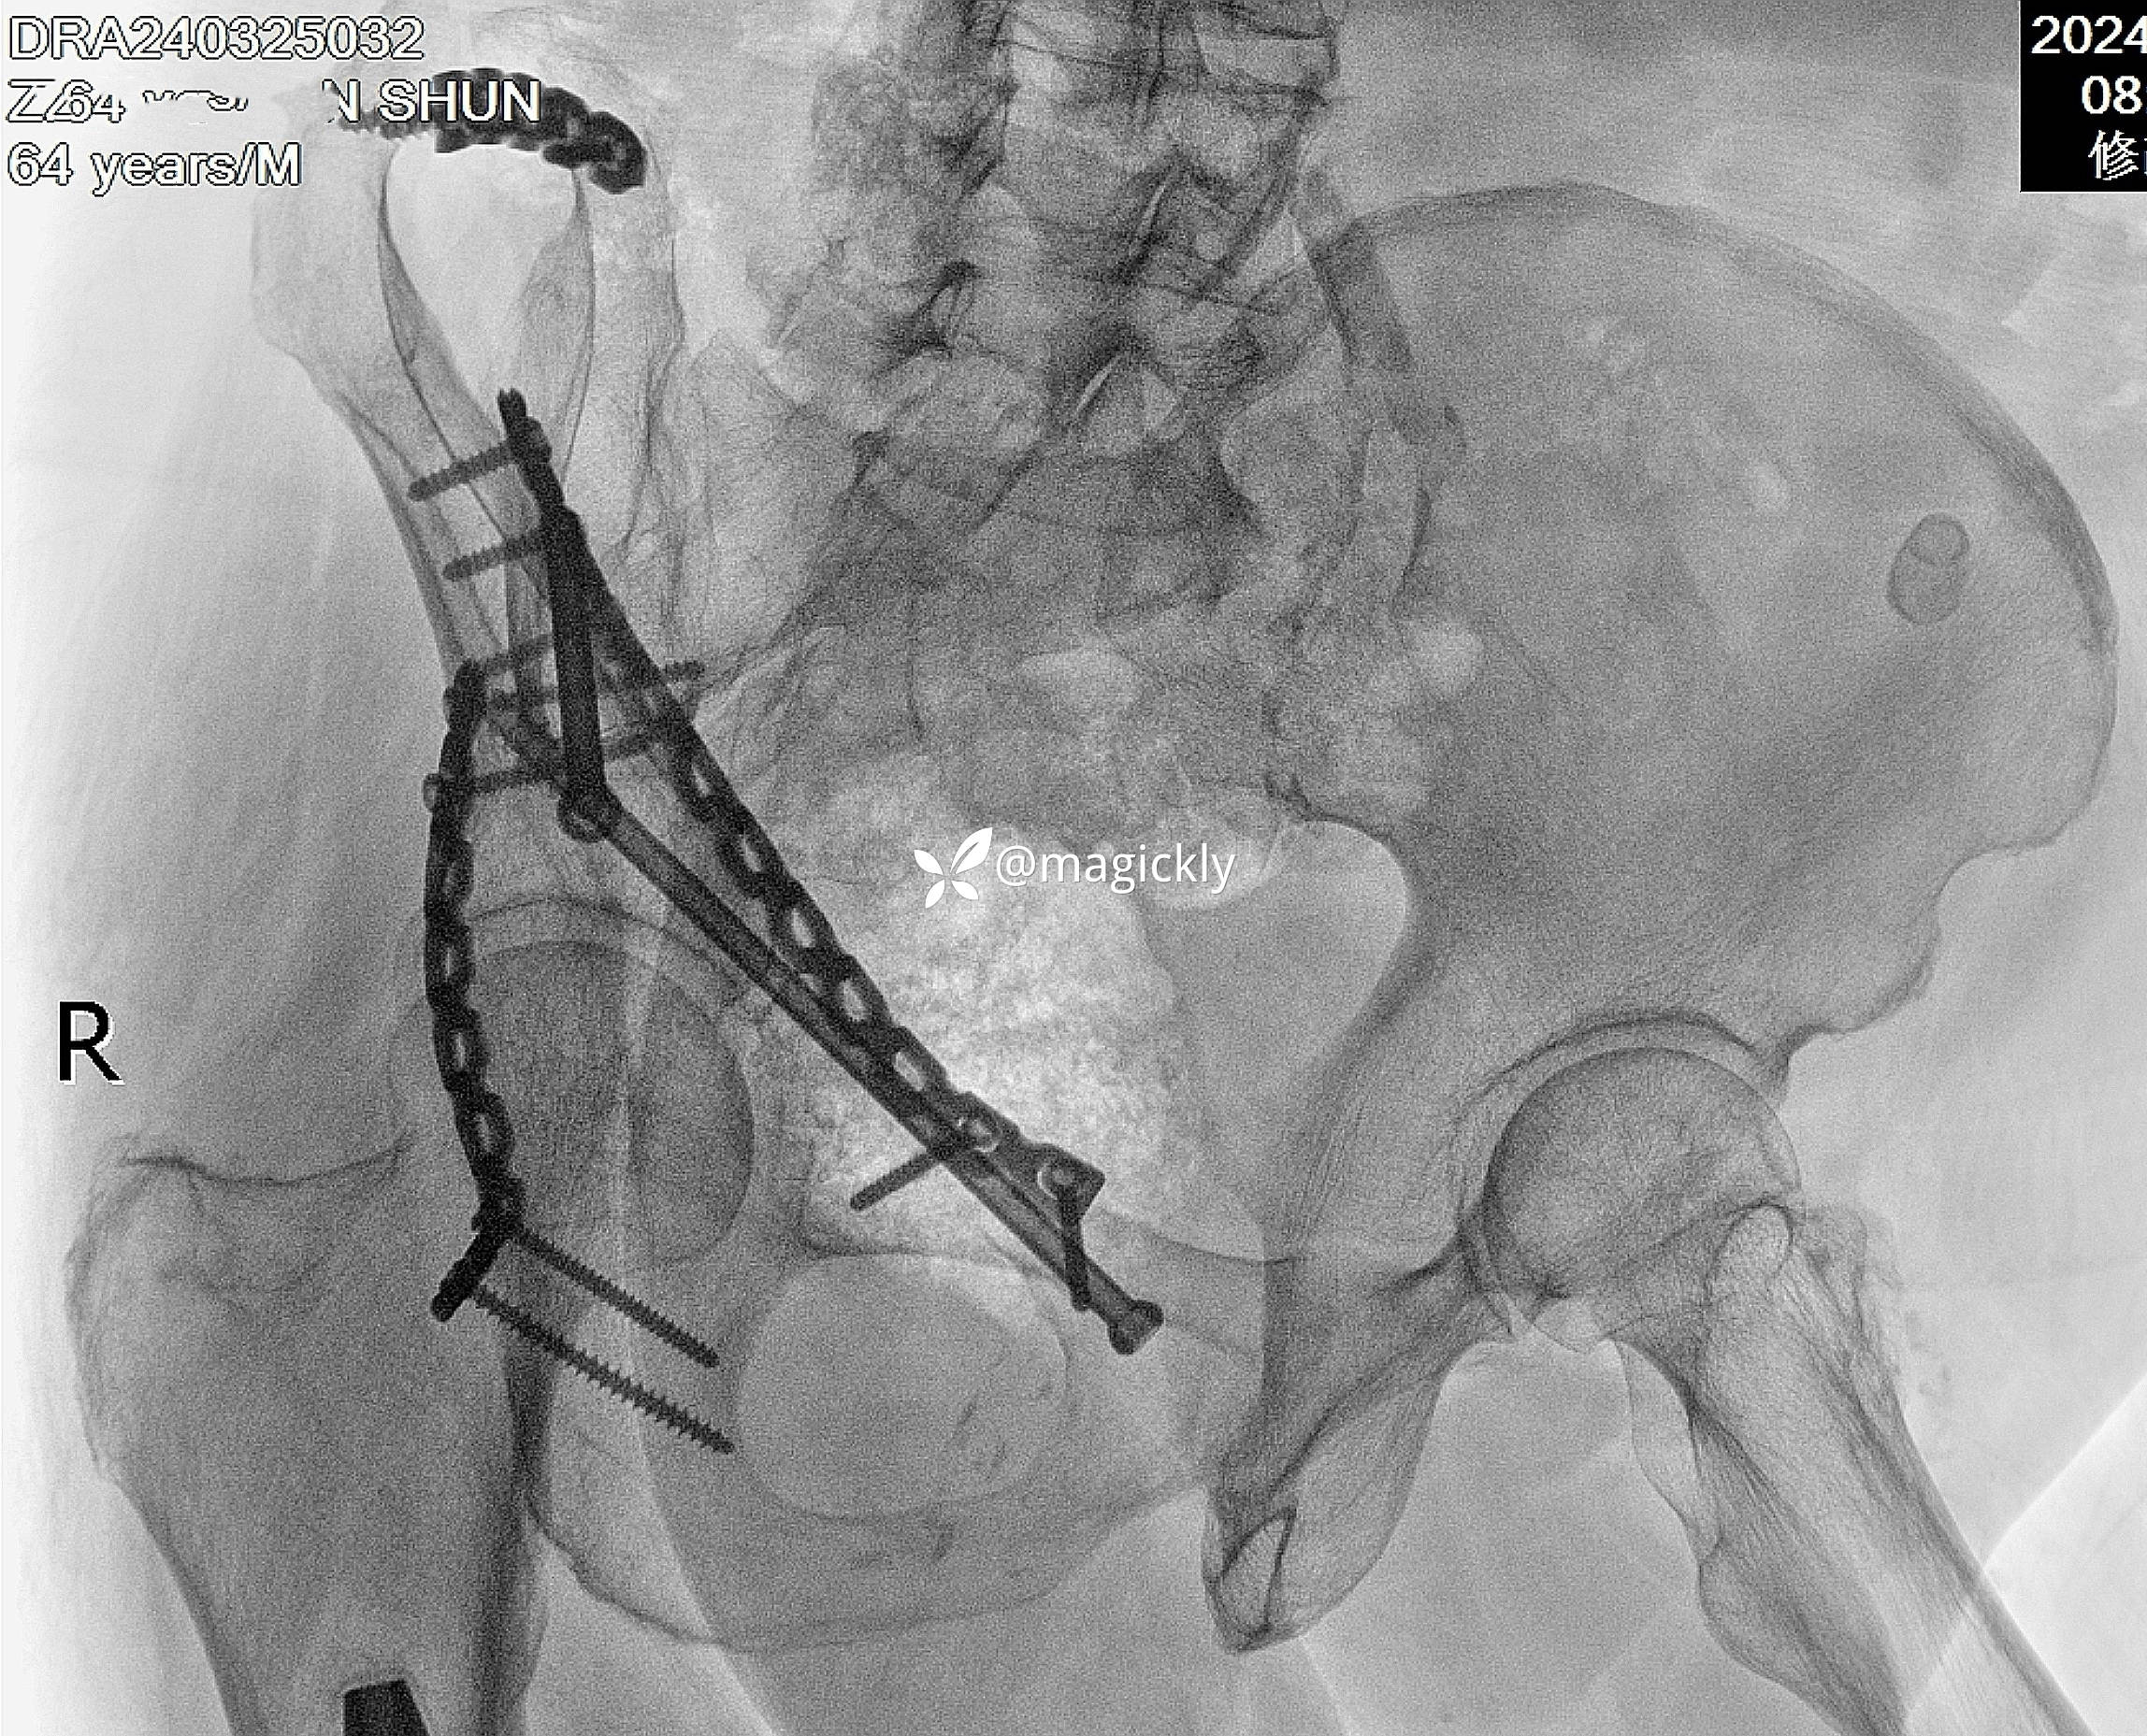

【治疗经过及结果】

img